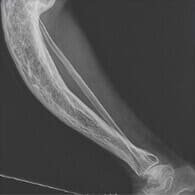

Eltörtem a lábam, és nagyon sokáig voltam kórházban rándulással, a szakember azt mondta, hogy járni fogok, de hozzá kell szoknom az időnkénti fájdalomhoz. Azonban kibírhatatlan volt a fájdalom, minden lépés olyan volt, mint egy megpróbáltatás. Az ízületek helyreállításához elkezdtem szedni az UltraVix kapszulát. A fájdalom gyorsan alábbhagyott, remélem, hamarosan teljesen elmúlik.